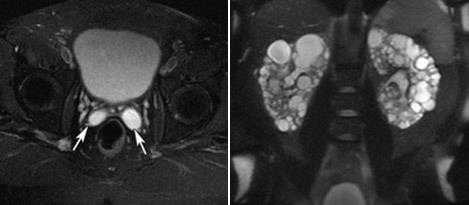

6. Аутосомно-доминантный поликистоз почек и семенных пузырьков.

Наличие кист в семенных пузырьках при аутосомно-доминантном поликистозе почек имеет большую клиническую значимость. При УЗИ данная патология может быть ошибочно интерпретирована как кисты простаты.

Клиническая картина поликистоза может включать в себя гемоспермию.

На представленных Т2-ВИ с жироподавлением определяются билатеральные кисты семенных пузырьков (а, аксиальная плоскость) и увеличение почек за счет множественных кист (б, фронтальная плоскость).